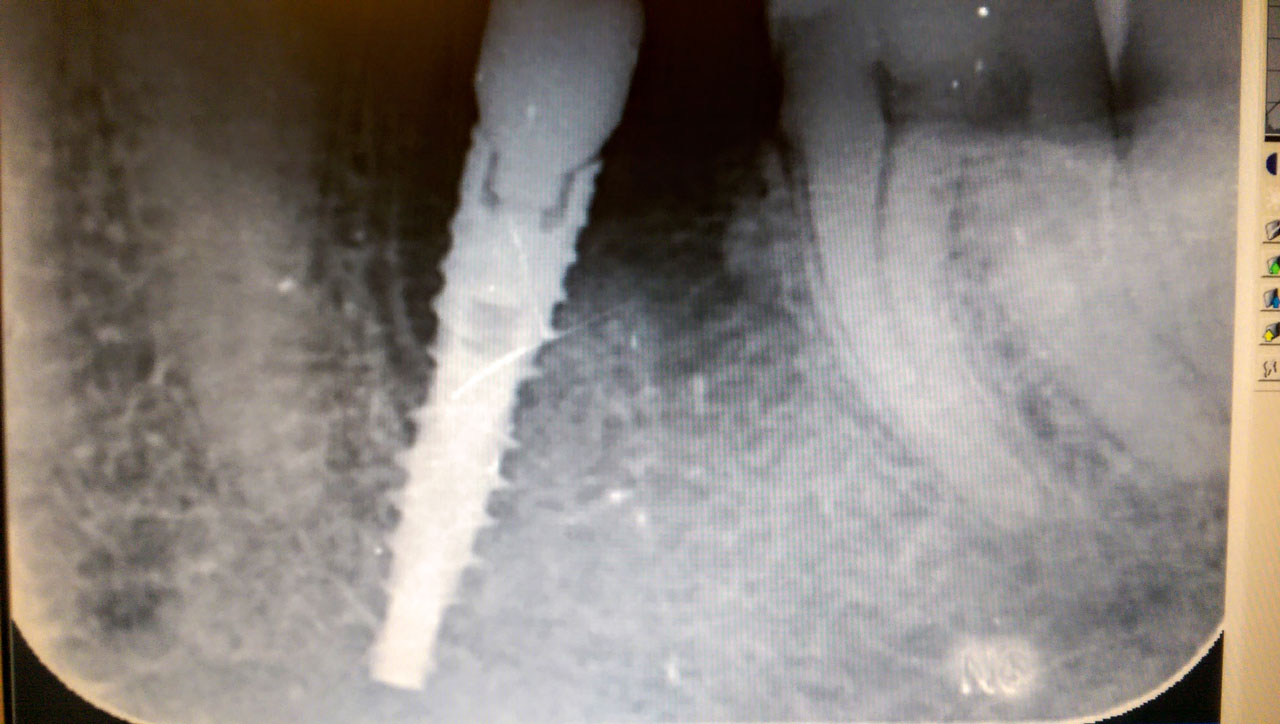

Régen a fogpótlás nem volt annyira egyszerű és gördülékeny, mint ma, ugyanis a kifejlesztett eljárásoknak és speciális elemeknek köszönhetően, igencsak gyorsan megalkotható egy újra kalibrált mosoly. Mindezt a svájci azonnal terhelhető implantátum teszi lehetővé, aminek applikálása csupán néhány napot vesz igénybe.

Az egészet Stephen Idhe professzor fejlesztette ki és az eljárás sikerét az elmúlt 10 évben implantált betegek magas száma is bizonyítja. Az azonnal terhelhető implantátum létezése hihetetlenül hangzik, de valóban létezik és már Budapesten a Relax Dental Center jóvoltából igénybe vehető. Az egész művelet sikere százalékban kifejezve 98,2%-os, de persze, hogy mindez megvalósuljon az orvosoknak folyamatosan frissíteniük kell meglévő tudásukat.

Az IHDE azonnal terhelhető implantátum beültetése speciális tudást és felszerelést igényel, de ha mindez megvan, akkor foghúzást követően rögtön be lehet ültetni a csapot. Ha szeretne megbizonyosodni a szép végeredményről, amit 72 órán belül garantálnak, akkor nézze meg az esetbemutató képeket a honlapon.